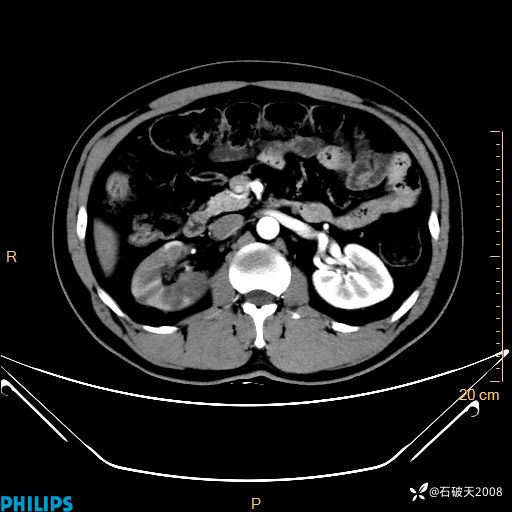

冠状位